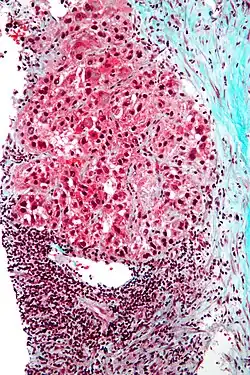

Pathology

Macroscopically, liver cancer appears as a nodular or infiltrative tumor. The nodular type may be solitary (large mass) or multiple (when developed as a complication of cirrhosis). Tumor nodules are round to oval, gray or green (if the tumor produces bile), well circumscribed but not encapsulated. The diffuse type is poorly circumscribed and infiltrates the portal veins, or the hepatic veins (rarely).[20]

Microscopically, the four architectural and cytological types (patterns) of hepatocellular carcinoma are: fibrolamellar, pseudoglandular (adenoid), pleomorphic (giant cell), and clear cell. In well-differentiated forms, tumor cells resemble hepatocytes, form trabeculae, cords, and nests, and may contain bile pigment in the cytoplasm. In poorly differentiated forms, malignant epithelial cells are discohesive, pleomorphic, anaplastic, and giant. The tumor has a scant stroma and central necrosis because of the poor vascularization.[46] A fifth form – lymphoepithelioma like hepatocellular carcinoma – has also been described.[47][48]

-

Well-differentiated HCC -

Moderately differentiated HCC -

Poorly differentiated HCC